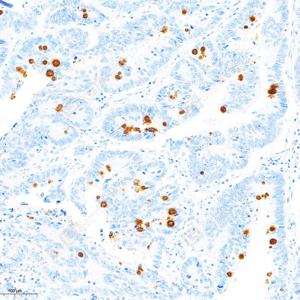

IHC检测MUC2蛋白(货号 GB15344). 样品: 人小肠, 4%多聚甲醛 (货号G1101) 固定12-24小时. 抗原修复: 柠檬酸抗原修复液(干粉, pH 6.0) (G1201), 高压锅均匀喷气计时2分钟. —抗: 1: 1000稀释, 4℃ 孵育过夜. 二抗: S-vision免疫组化多聚二抗(山羊抗兔),即用型 (货号G1302), 室温孵育20分钟. |